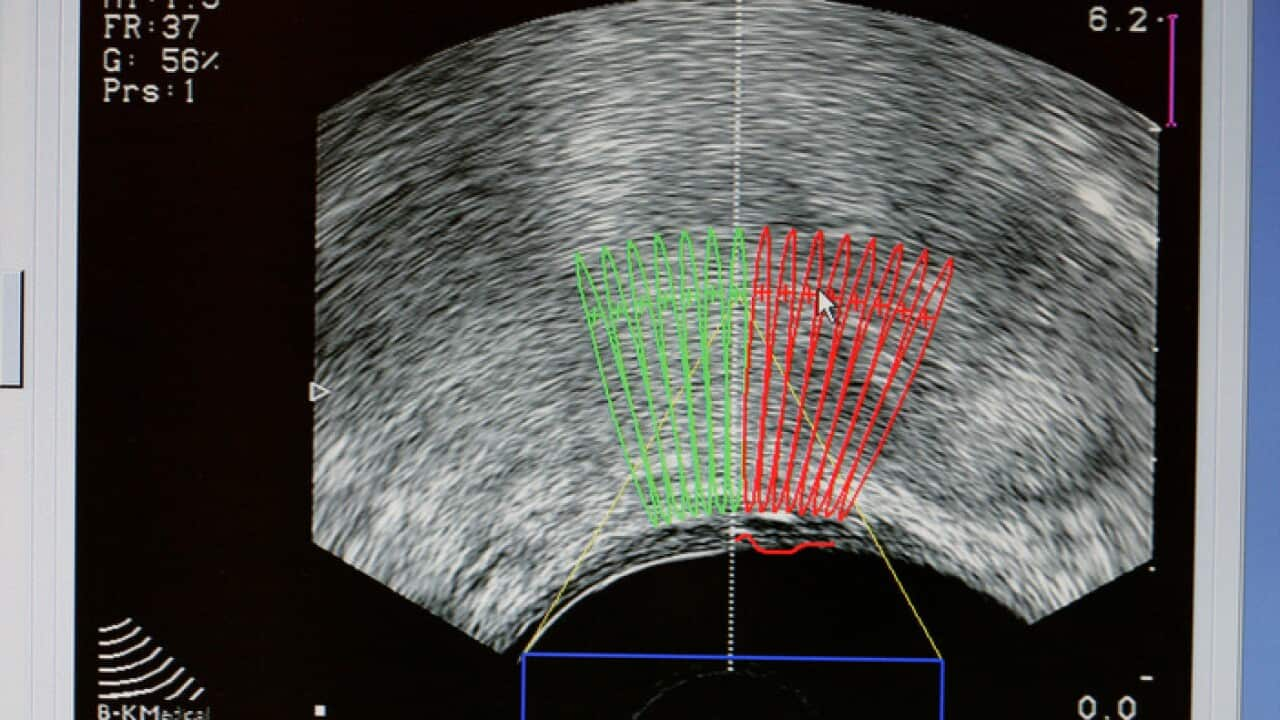

Prostate cancer ultrasound scan Source: Getty